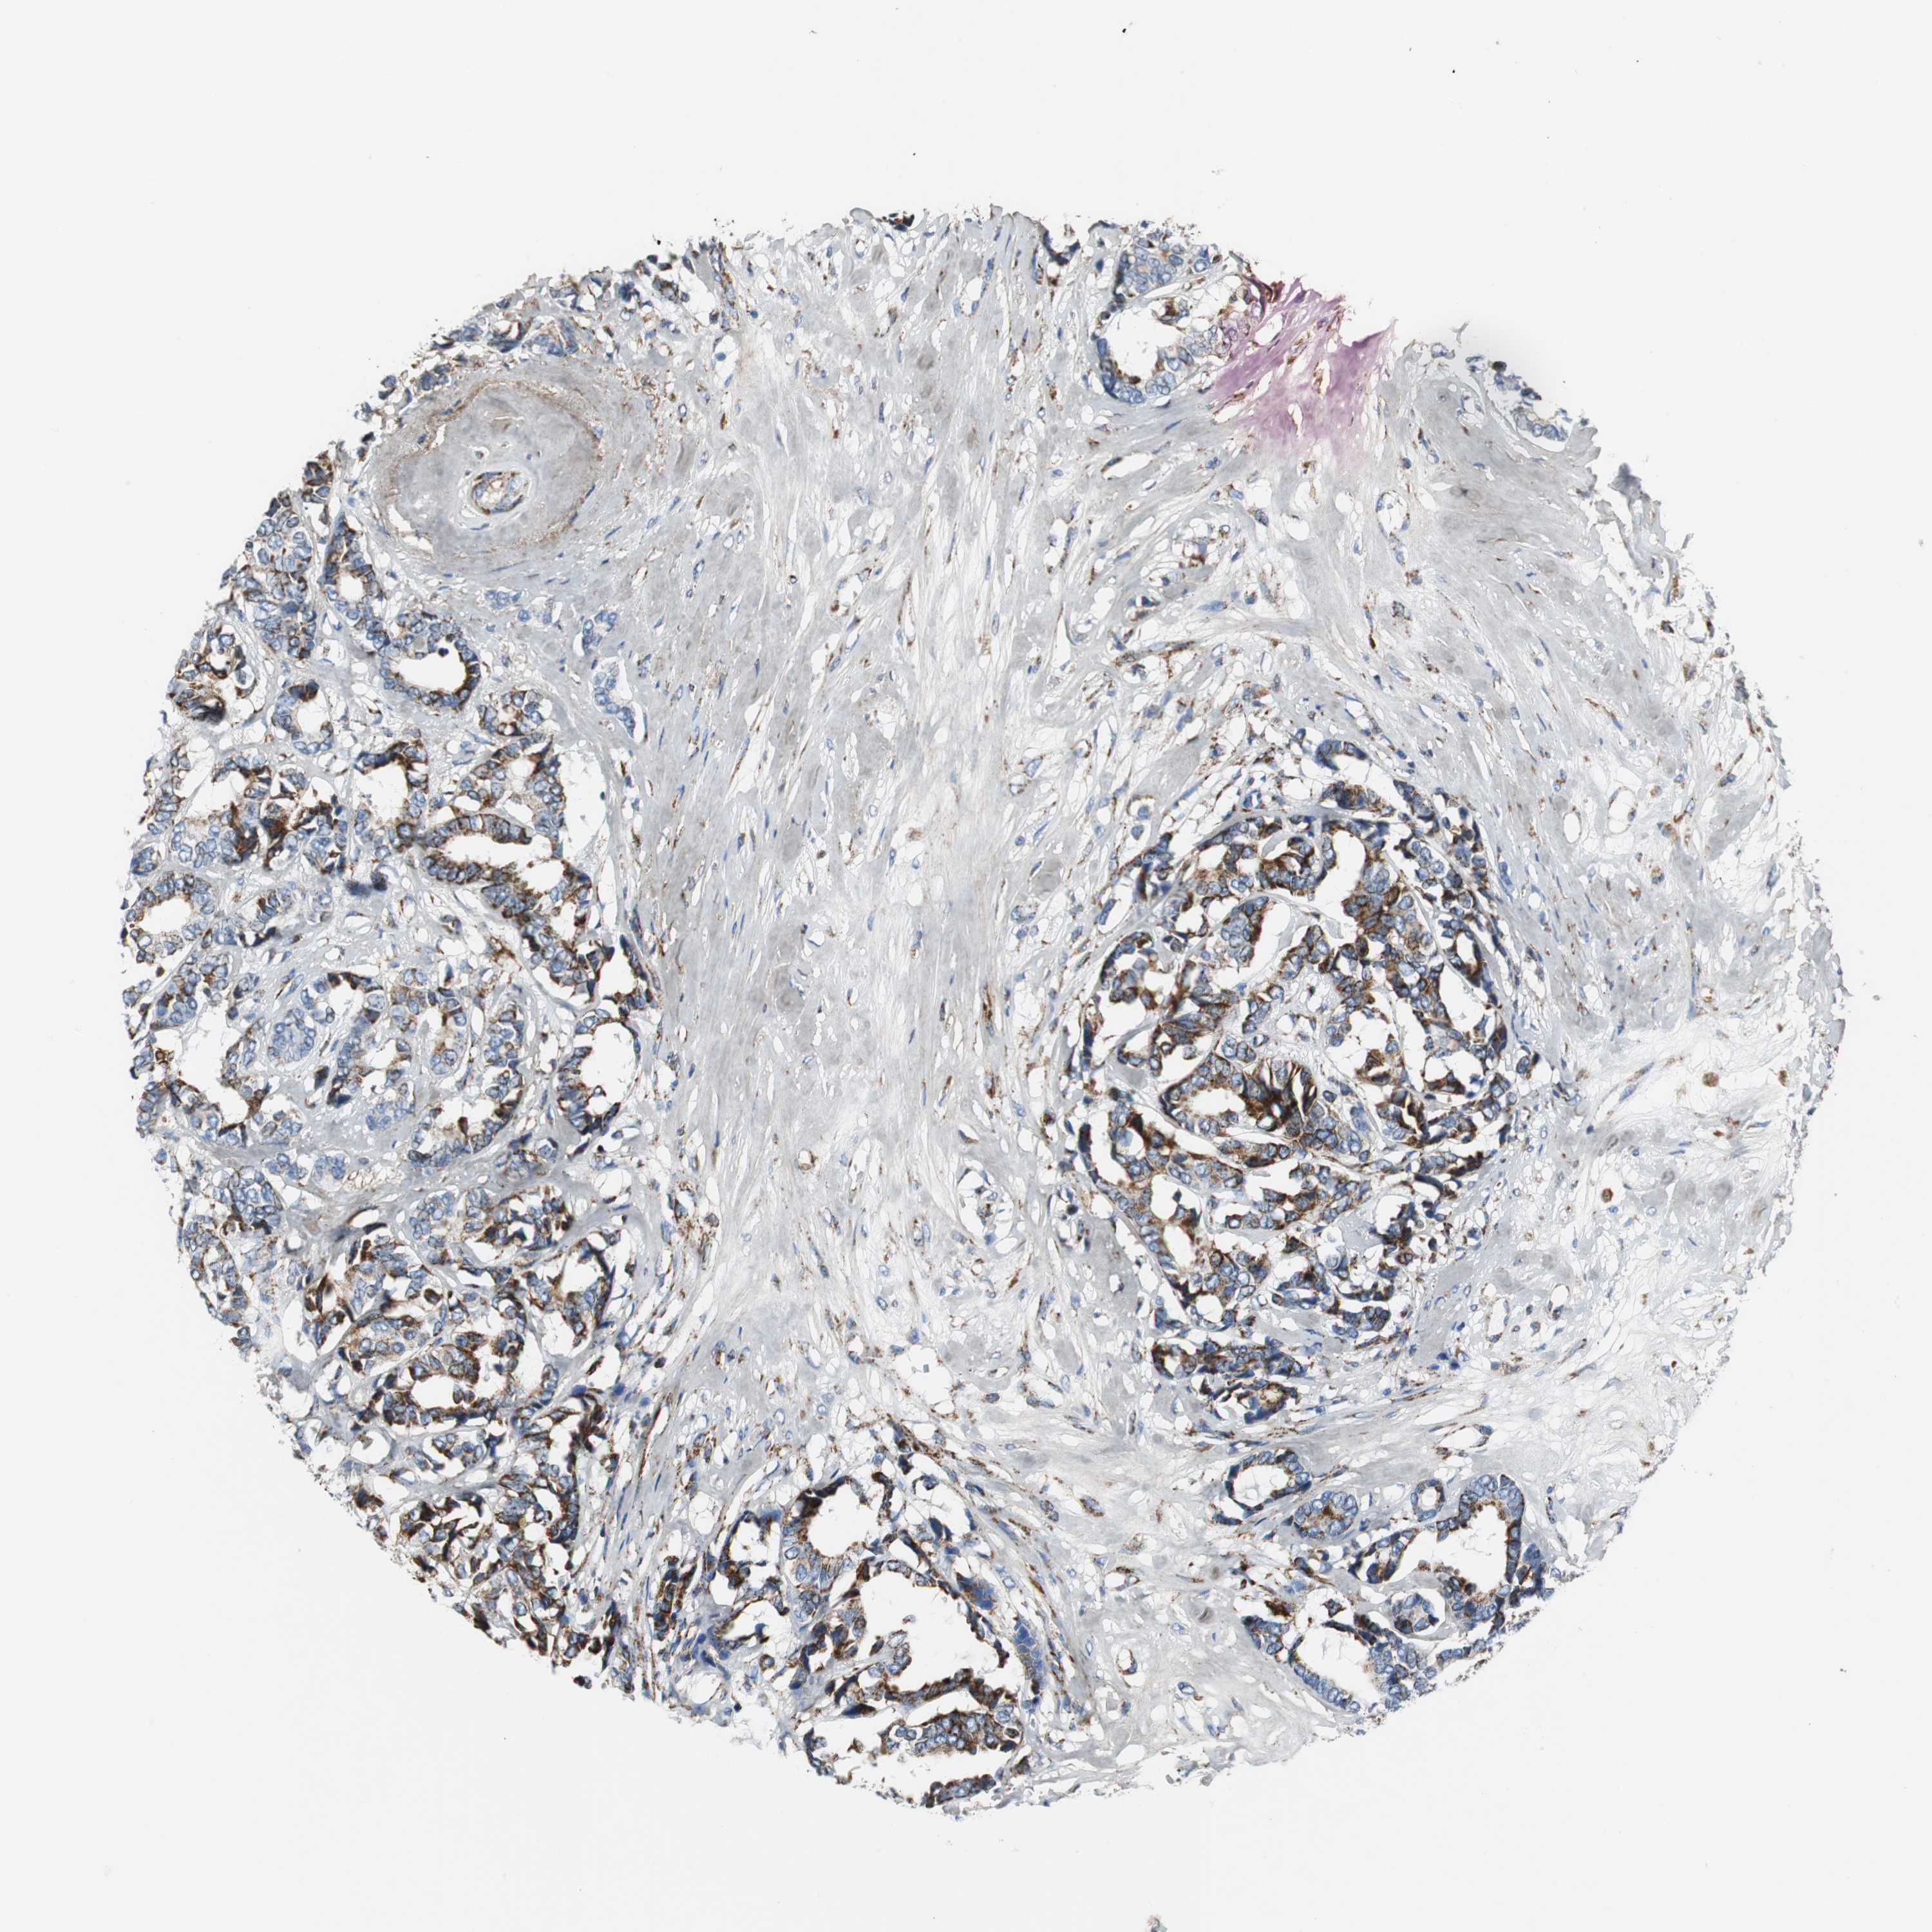

BRCA TCGA BRCA VALIDATION PROTEIN EXPRESSION

ANTIBODIES

AND

VALIDATION